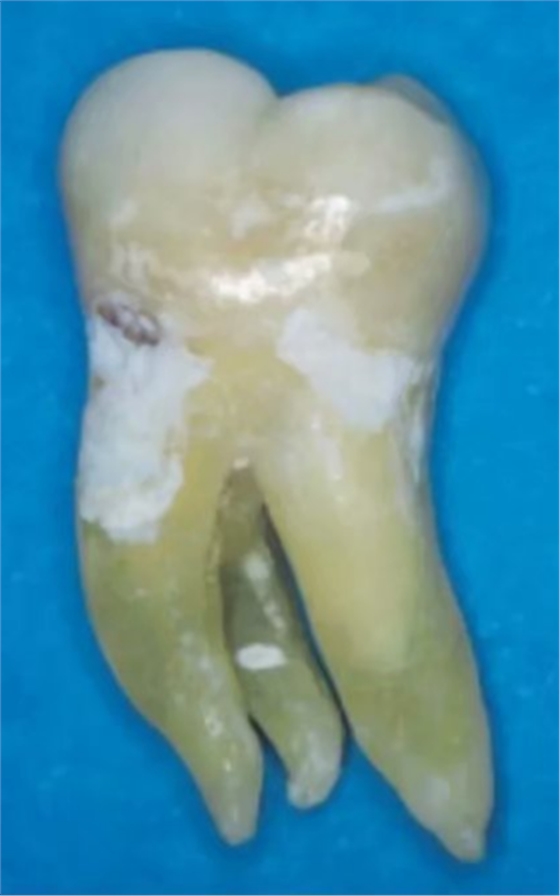

異于雙根的下頜第一磨牙的解剖形態(tài)變異主要為存在一個(gè)額外的位于遠(yuǎn)舌側(cè)【radix entomolaris(RE)】或近頰側(cè)【radix paramolaris(RP)】的牙根(圖 13)。在白種人和非洲人中發(fā)生這種牙根異常形態(tài)的概率不超過 5%,然而在黃種人中(比如中國(guó)人、因紐特人、印第安人)遠(yuǎn)舌根發(fā)生率在 5%至超過 30%之間。位于頰側(cè)的近頰根罕見,發(fā)生率低于 0.5%(。遠(yuǎn)舌根的外形大小可從小圓錐形變化至正常長(zhǎng)度和根管的“成熟的”牙根。

一般來說,遠(yuǎn)舌根比遠(yuǎn)頰根和近中根小,可能獨(dú)立于或部分融合于其他牙根。臨床治療過程中,當(dāng)懷疑存在額外的牙根時(shí),需要根據(jù)準(zhǔn)確的放射學(xué)診斷、臨床檢查、開髓洞型預(yù)備進(jìn)行判斷。在術(shù)前的放射片中,若遠(yuǎn)中根輪廓或根管的視野或外形不清楚,可能表明存在“隱藏的”牙根。在近中或遠(yuǎn)中成 30 度角的方向上拍攝第二張放射片,通常可以顯示遠(yuǎn)舌根的輪廓。

使用牙周探針對(duì)牙冠或牙頸部形態(tài)進(jìn)行臨床檢查有助于發(fā)現(xiàn)額外的牙根。一個(gè)額外的牙尖(副磨牙結(jié)節(jié),tuberculum paramolare)或明顯突出的遠(yuǎn)頰或遠(yuǎn)舌小葉,伴有頸部的突出,可能表明存在額外的牙根。遠(yuǎn)舌根的根管口位于主要的遠(yuǎn)中根管的近舌側(cè),因此開髓洞型需要預(yù)備成矩形或梯形。使用牙髓探針仔細(xì)檢查髓室底的暗色的發(fā)育溝,可以精確的定位遠(yuǎn)舌根根管口。